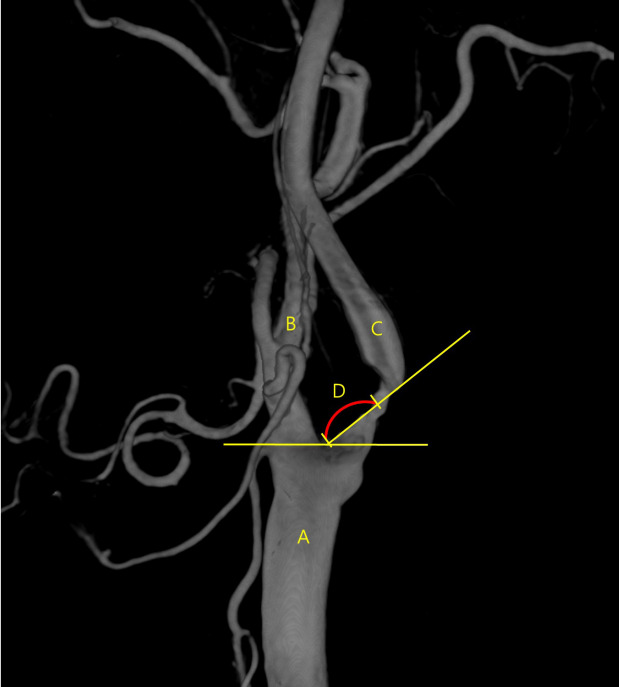

Results: Among patients who received PPLIs, the mean degree of stenosis was 80.5% (95% confidence interval [CI]: ±10.74, 51-98%). The mean distance from the common carotid artery bifurcation to the most stenotic lesion (CSD) was 8.3 mm (95% CI: ±0.97, 6.3-10.2 mm); the mean angle between the internal carotid artery and common carotid artery (CCA) trunk (IAG) was 65.6° (95% CI: ±2.39, 61-70°). Among patients who did not receive PPLIs, the mean degree of stenosis was 84.0% (95% CI: ±8.96, 70-99%). The mean CSD was 5.9 mm (95% CI: ±1.83, 1.9-9.9 mm); the mean IAG was 60.4° (95% CI: ±4.41, 51-70°). The procedure time was longer in the PPLI group than in the no PPLI group (28.19 [n=39] vs. 18.88 [n=12] days) (P=0.057); the length of intensive care unit stay was shorter in the PPLI group (20.01 [n=36] vs. 28.10 [n=5] days) (P=0.132).

Conclusions: Targeted PPLI administration to the carotid bulb decreased aberrant heart rates and blood pressure changes induced by carotid stent deployment and balloon inflation. As CBR sensitivity increases with decreasing distance to the stenotic lesion from the CCA bifurcation, PPLIs may help stabilize patients during procedures for stenotic lesions closer to the CCA.